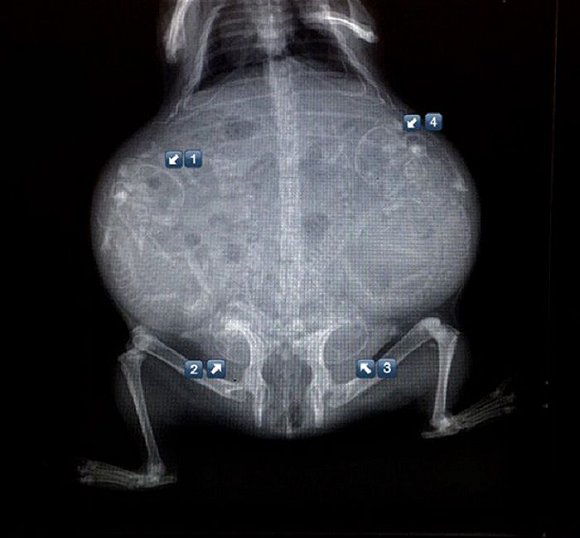

可爱又毛骨悚然 怀孕动物的X光片

人类之间分享母亲肚子里胎儿的X光片是一件非常常见的事情,但是,纵使你觉得自己对X光片已经见怪不怪,在看到了下面这些怀孕动物的X光片后你仍旧会说"哦我的天哪"。

以下就是一些动物在怀孕时的X光片。

2. 黑叶猴